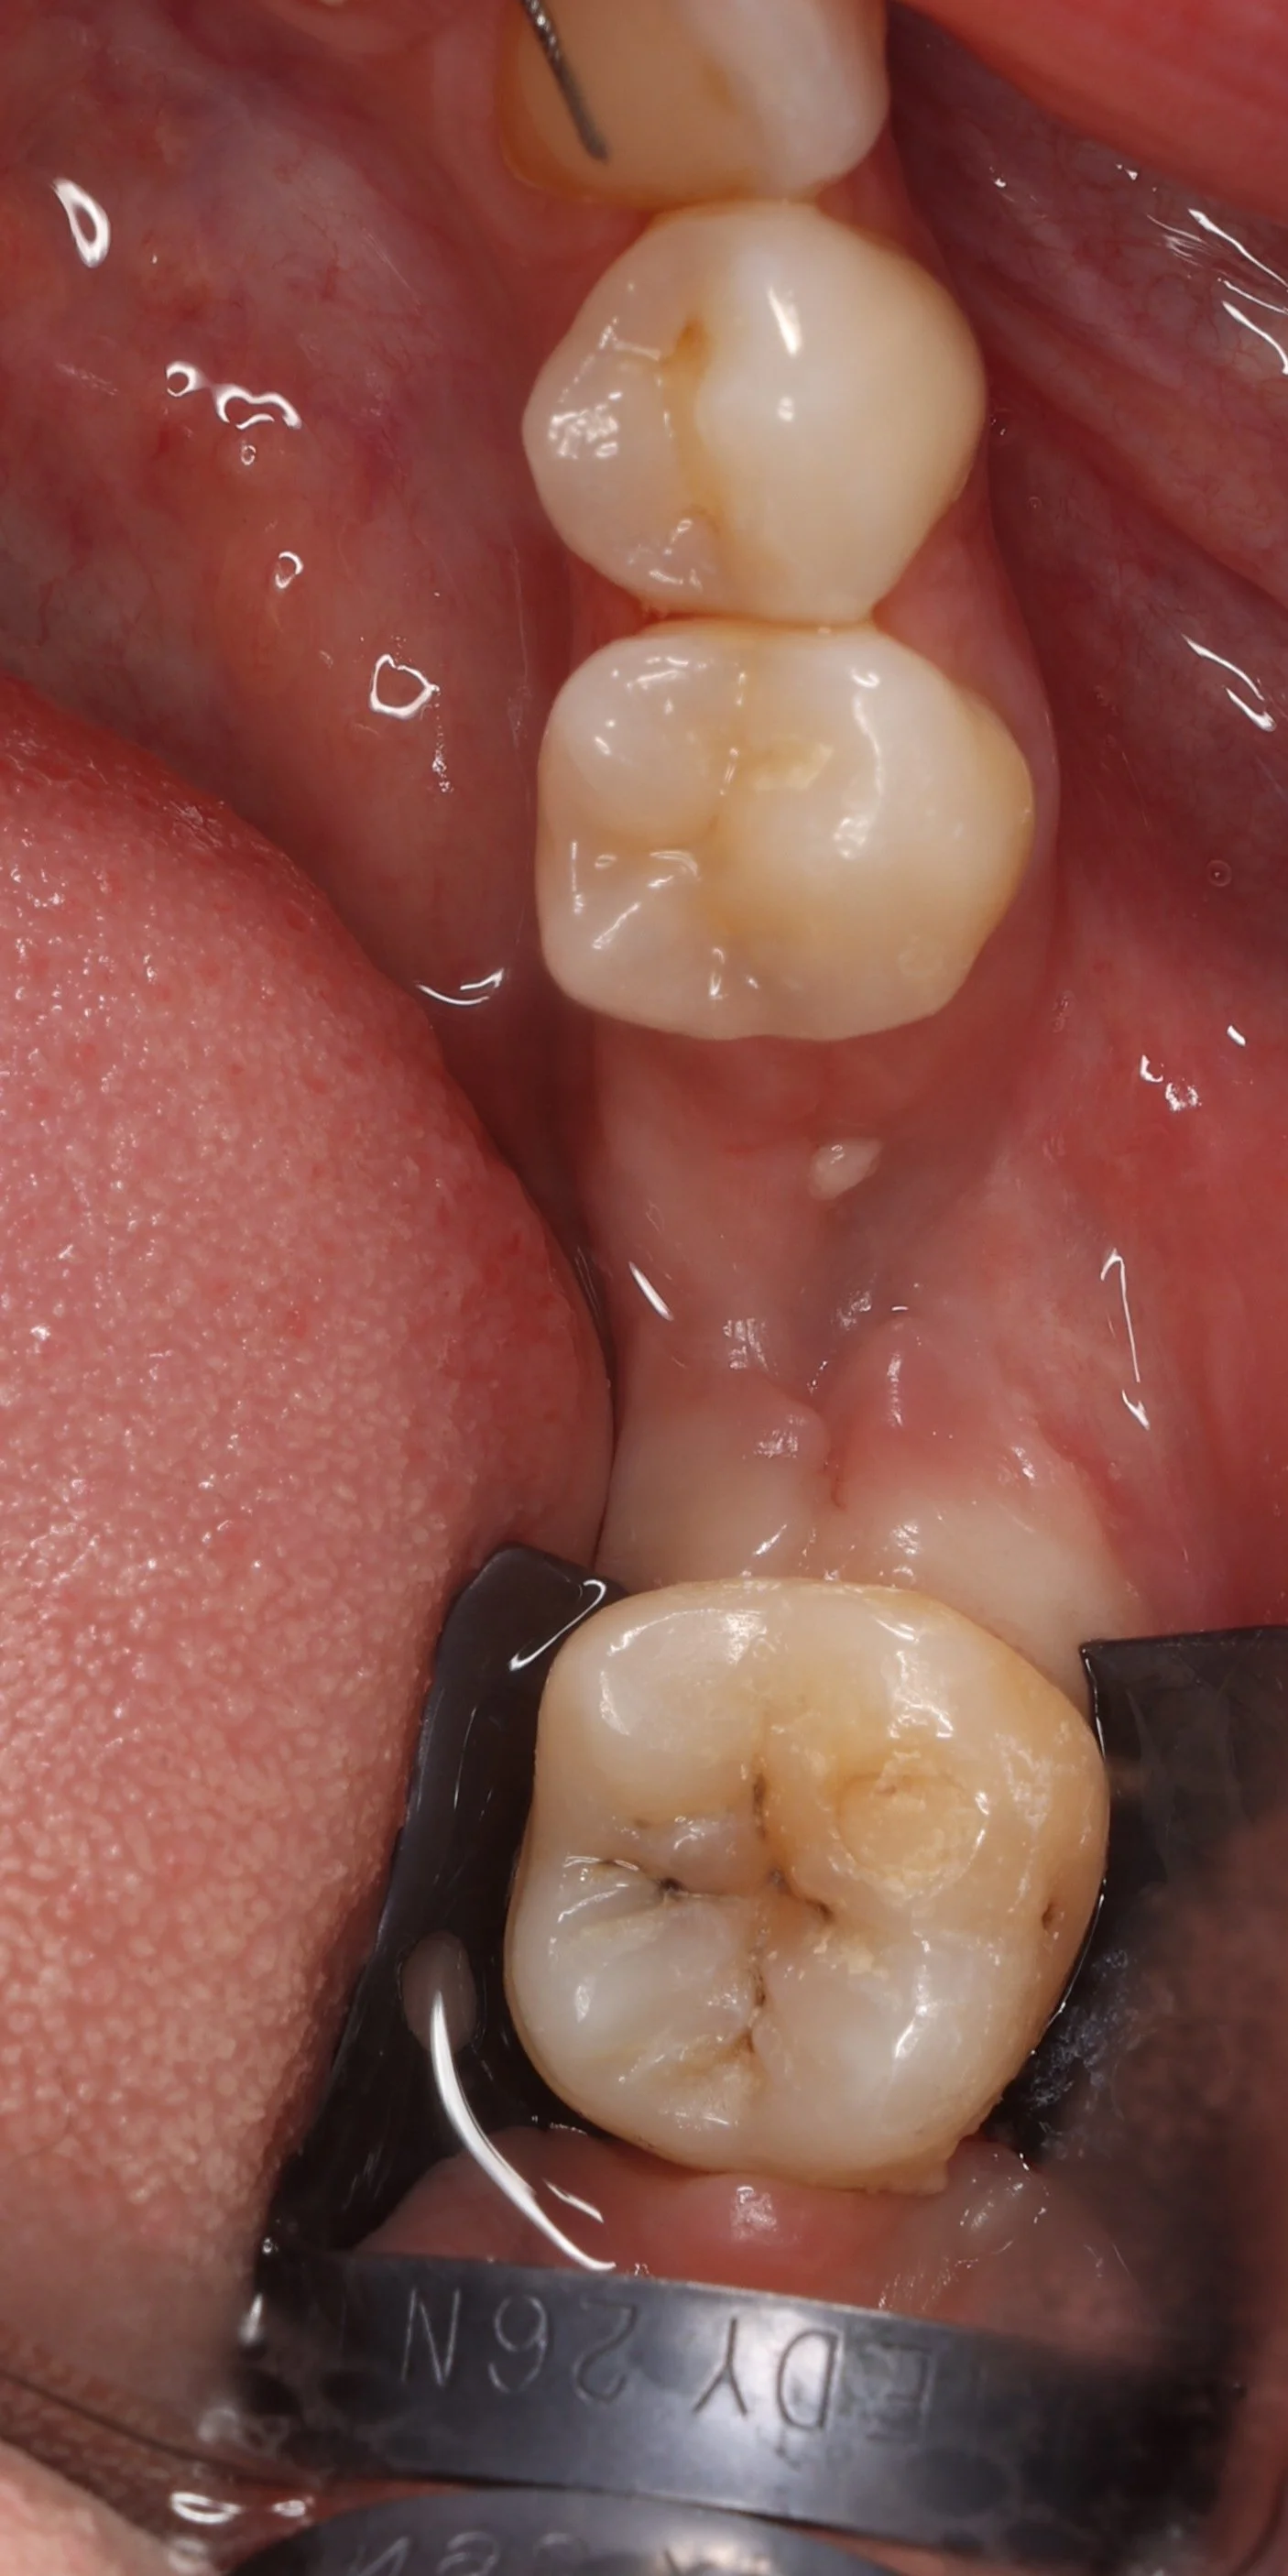

Relativement récents, les bridges collés cantilever postérieurs constituent une alternative fixe, fiable et véritablement minimalement invasive aux implants dans les secteurs postérieurs. Cette thérapeutique qui repose sur des indications bien précises est parfois débattue avec passion sur les réseaux sociaux ou dans les congrès scientifiques. Cependant des études cliniques existent, tout comme des recommandations validées dans des journaux internationaux. Leur succès repose sur des préparations et des principes biomécaniques rigoureux, pourtant simples à intégrer au quotidien. Cette intervention propose un guide clair et opérationnel incluant indications, étapes clés, protocoles d’adhésion et réglages occlusaux pour les mettre en œuvre avec confiance et reproductibilité.